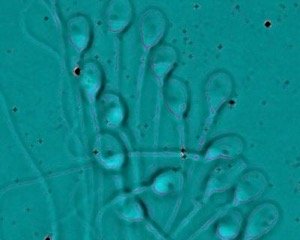

Σε αυτές τις περιπτώσεις, διαλέγουμε υγιή σπερματοζωάρια σε μικροσκόπιο μεγάλης διακριτικής ικανότητας. Κατόπιν, με μια ειδική βελόνα τρυπάμε το τοίχωμα του ωάριου εισάγοντας το σπερματοζωάριο. Την επόμενη μέρα περιμένουμε να δούμε την εξέλιξη και ποιότητα των εμβρύων.

IMSI (ενδοκυτταροπλασματική έγχυση μορφολογικά επιλεγμένων σπερματοζωαρίων)

Η μέθοδος επιλογής σπέρματος περιλαμβάνει την μορφολογική επιλογή του σπέρματος με υψηλής ανάλυσης μικροσκόπιο περίπου 5 φορές μεγαλύτερης ευκρίνειας.

Με τον τρόπο αυτό, επιλέγονται τα σπερματοζωάρια των οποίων το σχήμα και το μέγεθος υποδηλώνει καλή γενετική ποιότητα κάτι που απαιτεί εξειδικευμένη εκπαίδευση για τους εμβρυολόγους. Στη συνέχεια, τα σπερματοζωάρια εμφυτεύονται μέσα στα ωάρια με τη μέθοδο ICSI.